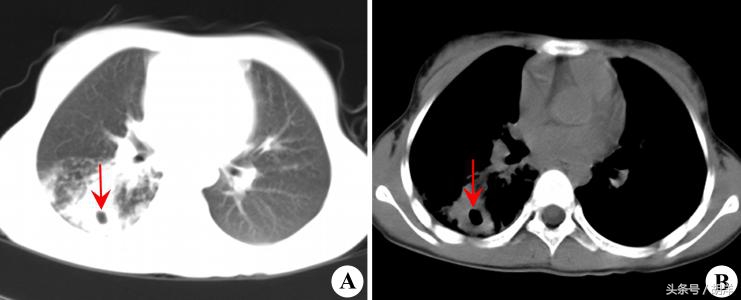

肺脓肿对于肺的位置有选择性

由于肺脓肿大部分是因为吸入肺外物质造成,因此肺脓肿的发生部位由吸入物的流经位置决定。人左右支气管并不是对称性的,右侧的支气管直,左侧的支气管比较弯,因此,吸入物更容易流入到右肺,而吸入大部分发生于晚间,所以肺脓肿就特别容易发生在靠近背部的肺叶,比如上叶后段和下叶背段。

肺脓肿是造成肺部空洞的多种疾病之一

厌氧菌具有极大的破坏力,感染肺组织后很容易造成坏死,坏死的组织会形成浓痰排出体外,肺上就会形成一个空洞,空洞里不是干的,会积存一些脓液,这个是肺脓肿的特征性表现,其他会形成肺空洞的疾病还有肺癌,肺结核等,是临床上常常需要鉴别的三大疾病。